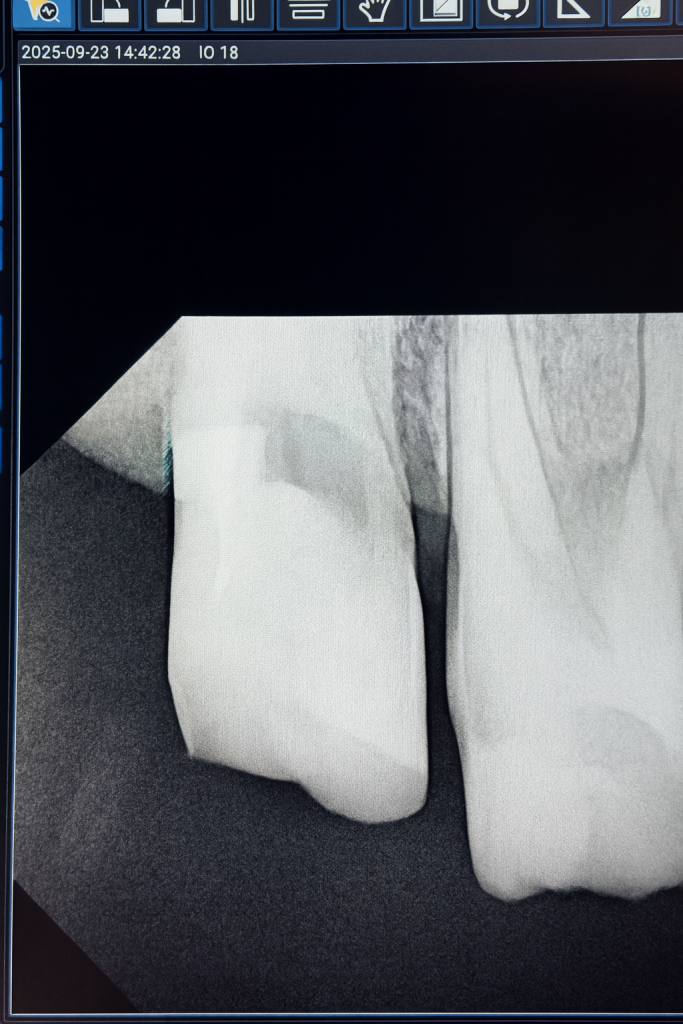

A patient reported with pain and structural compromise of a maxillary posterior tooth. The clinical and radiographic examination confirmed irreversible pulpitis with significant carious destruction extending subgingivally. The treatment plan involved root canal therapy under microscope guidance, followed by biomimetic reinforcement through DME and a cuspal coverage composite onlay.

- Obturation: Warm vertical compaction with bioceramic sealer provided dense, hermetic canal filling.

- Radiographic Assessment: Post-obturation radiograph revealed ideal canal filling.